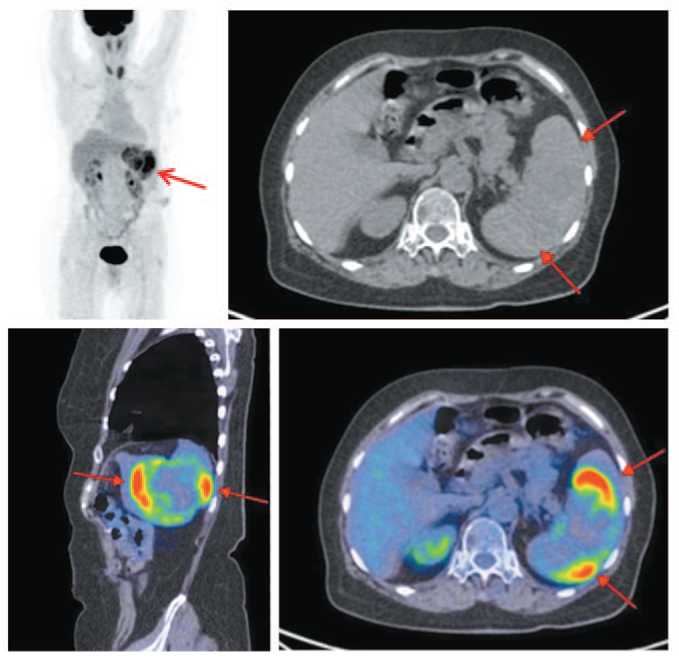

Больная К., 68 лет. Ранее, в ноябре 2016 г., ей выполнено экстренное оперативное вмешательство по поводу опухоли селезеночного угла, осложненной острой толстокишечной обтурационной непроходимостью. При интраоперационной ревизии выявлена стенозирующая опухоль селезеночного угла без признаков прогрессирования. Выполнена левосторонняя гемиколэктомия. При гистологическом исследовании обнаружена изъязвленная умеренно дифференцированная аденокарцинома с прорастанием всей стенки и врастанием в окружающую клетчатку. Метастазов в лимфоузлах и большом сальнике нет. Установлена IIb pT4bN0M0 стадия. В послеоперационом периоде проводилась адъювантная ПХТ по схеме FOLFOX – 6 циклов. В процессе динамического наблюдения в соответствии с рекомендациями пациентке регулярно выполнялись ультразвуковое исследование (УЗИ) и КТ органов брюшной полости. В октябре 2018 г. выполнена рентгеновская КТ (РКТ) органов брюшной полости и забрюшинного пространства. Селезенка увеличена: 130×60 мм, в венозной фазе в среднем и нижнем сегментах визуализируется зона пониженной плотности неоднородной структуры, с четкими, бугристыми полициклическими контурами – конгломерат из множественных округлых очагов размером 60×45 мм. Заключение: множественные метастазы в селезенку. С целью подтверждения диагноза и установления распространенности опухолевого процесса выполнена ПЭТ/КТ с 18-фтордезоксиглюкозой. На MIP ПЭТ и совмещенных ПЭТ/КТ в саггитальной и аксиальной проекциях определяется умеренное увеличение селезенки в краниокаудальном размере до 124×50 мм с четкими ровными контурами, неоднородной плотности за счет наличия сливных гиподенсных образований размером до 25×15 мм, общим размером 55×45 мм, с повышенной фиксацией радиофармпрепарата (РФП), SUVmax 6.52. Каких-либо отдаленных проявлений болезни не выявлено. Установлен диагноз: множественные изолированные метастазы в селезенку (рис. 1).

Рис. 1. Больная К., 68 лет. На MIP ПЭТ и совмещенных ПЭТ/КТ в саггитальной и аксиальной проекциях определяется умеренное увеличение селезенки неоднородной плотности за счет сливных гиподенсных образований размером до 25×15 мм с повышенной фиксацией РФП, SUVmax 6.52.

Fig. 1. Patient K., 68 years old. Sagittal and axial MIP positron emission tomography and combined positron emission tomography/computed tomography images showed an enlarged spleen of heterogeneous density due to the numerous hypodense lesions with the increased uptake of radiopharmaceutical, the size was 25×15 mm, SUVmax of 6.52.